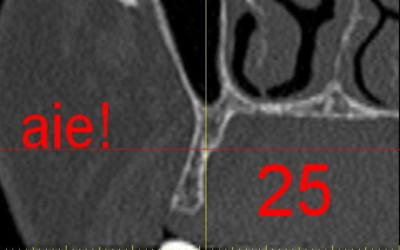

La première diapo est un essai pour justifier le concept (os non destiné à une utilisation greffe)

la deuxième est "tapée" dans une tête de femur de mauvais qualité (rejetée)

la troisième et suivante ce sont "les greffons" définitifs.

La précision 3D du scan est elle suffisante pour une adaptation passive sur l'os réel ?

La tu nous montres sur un stereolitique obtenu à partir du scan, ok ça colle mais en bouche ?